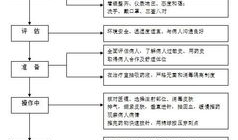

肌肉注射操作视频,步骤与技巧全解析

亲爱的读者们,你是否曾经好奇过,那些在医院里忙碌的医护人员是如何进行肌肉注射的?今天,就让我们一起揭开这个神秘的面纱,通过一段特...